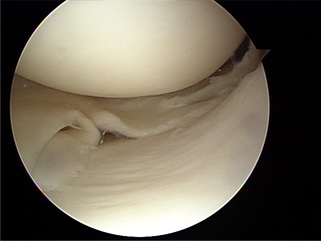

연골파열 사진